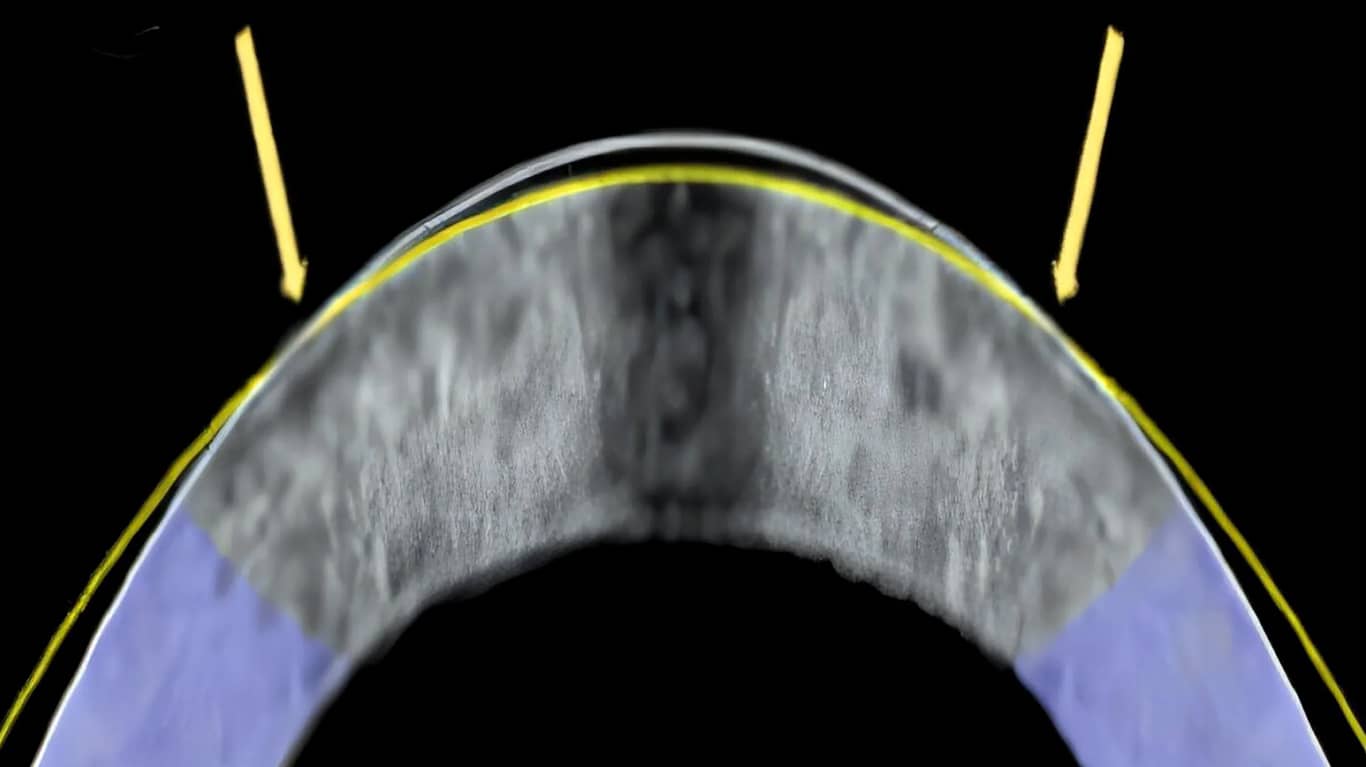

قرنیه یک ساختار آناتومیکی شفاف و بسیار سازمان‌ یافته است که بیشتر قدرت انکساری چشم را تأمین می‌ کند و به عنوان یک پنجره شفاف عمل می‌ کند و به تمرکز نور ورودی کمک می‌ کند. این سطح از الیاف کلاژن فشرده ساخته شده و به گونه‌ ای طراحی شده است که قوی و صاف باشد. وقتی نور وارد چشم می‌ شود، قرنیه اولین عدسی است که به آن برخورد می‌ کند و در اینجاست که بیشتر خمیدگی نور (انکسار) رخ می‌ دهد تا نور را روی شبکیه در پشت چشم متمرکز کند. تغییرات طبیعی، نقص‌ های مادرزادی، تروما و آسیب‌ شناسی‌ های مختلف می‌ توانند شکل، پایداری ساختاری و شفافیت قرنیه را تغییر دهند و منجر به اختلال در بینایی شوند. چشم زمانی دچار مشکلات بینایی از جمله نزدیک‌ بینی، دوربینی و آستیگماتیسم و سایر بیماری‌ ها می‌ شود که انحنای قرنیه تغییر کند، یعنی خیلی شیب‌ دار، خیلی صاف یا خیلی ناهموار شود. در ایالات متحده، نزدیک‌ بینی و نزدیک‌ بینی بالا بیش از 40٪ از جمعیت را تحت تأثیر قرار می‌ دهد. مداخله جراحی برای درمان عیوب انکساری رایج (یعنی نزدیک‌ بینی، دوربینی و آستیگماتیسم) معمولاً شامل اصلاح انحنای قرنیه با برداشتن فیزیکی بافت قرنیه است، به عنوان مثال، کراتومیلوزیس درجا با کمک لیزر (LASIK) و کراتکتومی فتورفراکتیو (PRK). از لیزر برای تغییر شکل قرنیه استفاده می‌ شود و این عمل به نور اجازه می‌ دهد تا به درستی روی شبکیه متمرکز شود. در حالی که برای کسانی که برای درمان مناسب هستند، لیزیک میزان موفقیت بالایی دارد. حدود ۹۵٪ از بیماران تنها چند روز پس از بهبودی از جراحی، عینک خود را کنار می‌ گذارند. این روش گران و تهاجمی است و برش قرنیه، یکپارچگی ساختاری چشم را تغییر می‌ دهد. درواقع لیزیک فقط یک روش فانتزی برای انجام جراحی سنتی است. این روش همچنان بافت را تراش می‌ دهد. نکته قابل توجه این است که هر دوی این روش‌ ها به طور دائم قدرت بیومکانیکی قرنیه را کاهش می‌ دهند و خطر بالقوه اکتازی پس از درمان ناشی از ساختار ضعیف قرنیه را افزایش می‌ دهند. سایر عوارض جانبی احتمالی شامل خیرگی بیش از حد و «هاله‌ ها» مرتبط با کاهش حدت بینایی در شب است. درمان‌ های غیرجراحی نیز دارای معایب قابل توجهی هستند. به عنوان مثال، ارتوکراتولوژی با قالب‌ گیری سطح قرنیه از طریق لنزهای تماسی سخت که در شب استفاده می‌ شوند، به طور موقت قدرت انکساری چشم را تغییر می‌ دهد. معایب این استراتژی شامل یک دوره درمان طولانی (معمولاً چند هفته) برای دستیابی به حدت بینایی نزدیک به امتروپیک؛ نیاز به نصب شبانه لنزهای «نگهدارنده» برای جلوگیری از عود شکل؛ و افزایش خطرات کراتیت باکتریایی، تک یاخته‌ ای و هرپسی است.

حال تصور کنید که بینایی خود را در کمتر از یک دقیقه اصلاح کنید! بدون لیزر، تیغه یا درد. دانشمندان یک تکنیک جدید و غیرتهاجمی توسعه داده‌ اند که قرنیه را تنها با استفاده از یک جریان الکتریکی خفیف و تغییر pH موقت تغییر شکل می‌ دهد. در آزمایش‌ های اولیه، این روش، نزدیک‌ بینی را بدون نیاز به جراحی سنتی معکوس کرد. و این می‌ تواند رادیکال‌ ترین پیشرفت در فناوری اصلاح بینایی از زمان لیزیک باشد. این روش نوظهور که می‌ تواند قرنیه را از طریق پتانسیل الکتریکی خفیف، که به عنوان تغییر شکل الکترومکانیکی (EMR) شناخته می‌ شود، تغییر شکل دهد، به تفصیل شرح داده شده است.

آنچه پیشنهاد می‌ شود، کار با ترکیب قرنیه برای تغییر شکل گنبد بدون حذف هیچ ماده‌ ای از آن است. قرنیه که عمدتاً از کلاژن ساخته شده است، به لطف چیدمان مولکول‌ ها و پروتئین‌ های باردار، شکل خود را حفظ می‌ کند. محققان کشف کردند که با اعمال یک جریان الکتریکی سطح پایین از طریق یک الکترود «لنز تماسی» پلاتینی با طراحی ویژه، می‌ توانند pH بافت را تغییر دهند و اسیدیته EMR از پالس‌ های الکتریکی کوچک برای تجزیه آب در سطح بافت به هیدروژن و اکسیژن استفاده می‌ کند و پروتون‌ هایی را آزاد می‌ کند که در بخشی از بافت قرنیه پخش می‌ شوند که به آن یکپارچگی ساختاری، توانایی هیدراتاسیون و سایر خواص مکانیکی می‌ دهد. هنگامی که پروتون‌ ها در سراسر سطح قرنیه پخش می‌ شوند، پیوندهای شیمیایی که الیاف کلاژن را در جای خود نگه می‌ دارند را مختل می‌ کنند و همچنین pH بافت قرنیه را تغییر می‌ دهند. بافت قرنیه را افزایش دهند، که آن را به اندازه کافی انعطاف‌ پذیر می‌ کند تا تغییر شکل دهد، مانند قرار دادن چیزی در قالب. در این مورد، قالب، لنز پلاتینی است. سپس، هنگامی که جریان متوقف می‌ شود و pH به حالت عادی بر می‌ گردد،  این لحظه‌ ای است که قرنیه قابل قالب‌ گیری می‌ شود. هنگامی که با یک قالب فلزی مانند لنز تماسی شکل داده می‌ شود، با خاموش شدن پالس‌ های الکتریکی، به شکل جدید "قفل" می‌ شود و پاسخ فیزیولوژیکی طبیعی بدن، pH قرنیه را به مقدار طبیعی خود بازمی‌ گرداند. کل این فرآیند حدود یک دقیقه طول می‌ کشد، نیازی به برش یا برداشتن بافت ندارد و تاکنون هیچ آسیب ساختاری یا مرگ سلولی در نمونه‌ های آزمایش شده نشان نداده است. و محققان معتقدند که EMR می‌ تواند جایگزین جراحی لیزیک شود. این فرآیند همچنین نویدبخش معکوس کردن کدورت قرنیه ناشی از مواد شیمیایی بود، وضعیتی که فقط با پیوند کامل قابل درمان است.